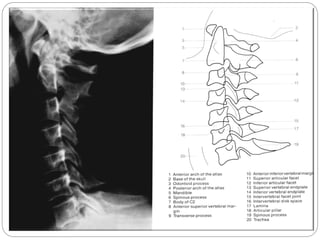

Aspectos Característicos da Cervical

Todas as Vértebras cervicais Possui três forames cada.

C1 ou Atlas Não tem corpo mas tem arco anterior, não tem processo espinhoso, mais massa lateral (pilares articulares).

C2 ou Áxis Possui o Processo odontóide (dente) .

C6 Processos espinhoso curtos com extremidades bífidas.

C7 Chamada vértebra proeminente devido ao seu longo processo espinhoso

1, Corpo Vertebral (T1). 2, Processo Espinhoso C7. 3, Lâmina do arco vertebral. 4, Processo articular inferior. 5, processo articular superior. 6, Processo Espinhoso C2. 7, Processo odontóide (ou dente do áxis). 8, Arco anterior do atlas (C1). 9, Traquéia

Aspectos Característicos daCervical Todas as Vértebras cervicais Possui três forames cada. C1 ou Atlas Não tem corpo mas tem arco anterior, não tem processo espinhoso, mais massa lateral (pilares articulares). C2 ou Áxis Possui o Processo odontóide (dente) . C6 Processos espinhoso curtos com extremidades bífidas. C7 Chamada vértebra proeminente devido ao seu longo processo espinhoso

1, Corpo Vertebral(T1). 2, Processo Espinhoso C7. 3, Lâmina do arco vertebral. 4, Processo articular inferior. 5, processo articular superior. 6, Processo Espinhoso C2. 7, Processo odontóide (ou dente do áxis). 8, Arco anterior do atlas (C1). 9, Traquéia